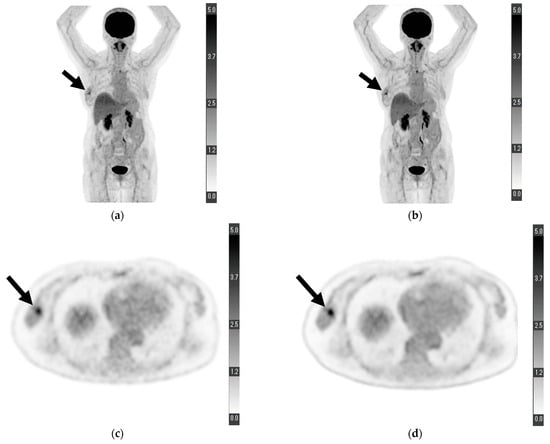

For “depiction of primary lesion”, the average score provided by reader 1 was higher for DL-PET than for cPET; however, no significant difference was observed (4.673 ± 0.695 vs. 4.455 ± 0.857, p = 0.121). Conversely, the score provided by reader 2 for DL-PET was significantly higher than that for cPET (4.364 ± 0.969 vs. 4.000 ± 1.089, p = 0.049). The scores of readers 1 and 2 for DL-PET were significantly higher than those for cPET in terms of “noise” (reader 1, 4.782 ± 0.498 vs. 4.073 ± 0.663, p < 0.001; reader 2, 4.491 ± 0.573 vs. 3.855 ± 0.621, p < 0.001), “clarity of mammary gland” (reader 1, 4.309 ± 0.836 vs. 3.909 ± 0.727, p = 0.003; reader 2, 4.109 ± 0.737 vs. 3.291 ± 0.737, p < 0.001), and “overall image quality” (reader 1, 4.636 ± 0.557 vs. 4.073 ± 0.663, p < 0.001; reader 2, 4.473 ± 0.539 vs. 3.904 ± 0.470, p < 0.001). The relevant data are shown in Table 2. Figure 1 shows a sample PET from a patient with some visual analysis scores higher in DL-PET than in cPET.

Figure 1.

Maximum-intensity projection of (a) conventional positron emission tomography (PET) reconstruction and (b) deep learning (DL) PET restoration of a woman in her 60 s with invasive ductal carcinoma in the right breast (arrows): invasive diameter, 15 mm; nuclear grade, 2; lymphatic invasion, negative; vascular invasion, negative; estrogen receptor, positive; progesterone receptor, positive; HER2 receptor, positive; Ki-67 staining, 25.5%; and nodal stage, 0. Axial view of a tumor cross-section for the same woman using (c) cPET reconstruction and (d) DL-PET restoration. Images were scored on a five-point scale from 1 = extremely poor to 5 = excellent. The scores of reader 1 for “depiction of the primary lesion”, “noise”, “clarity of mammary gland”, and “overall image quality” were 4, 5, 5, and 5 for cPET and 5, 5, 5, and 5 for DL-PET, respectively; the scores of reader 2 were 3, 4, 4, and 4 for cPET and 5, 5, 5, and 5 for DL-PET, respectively.